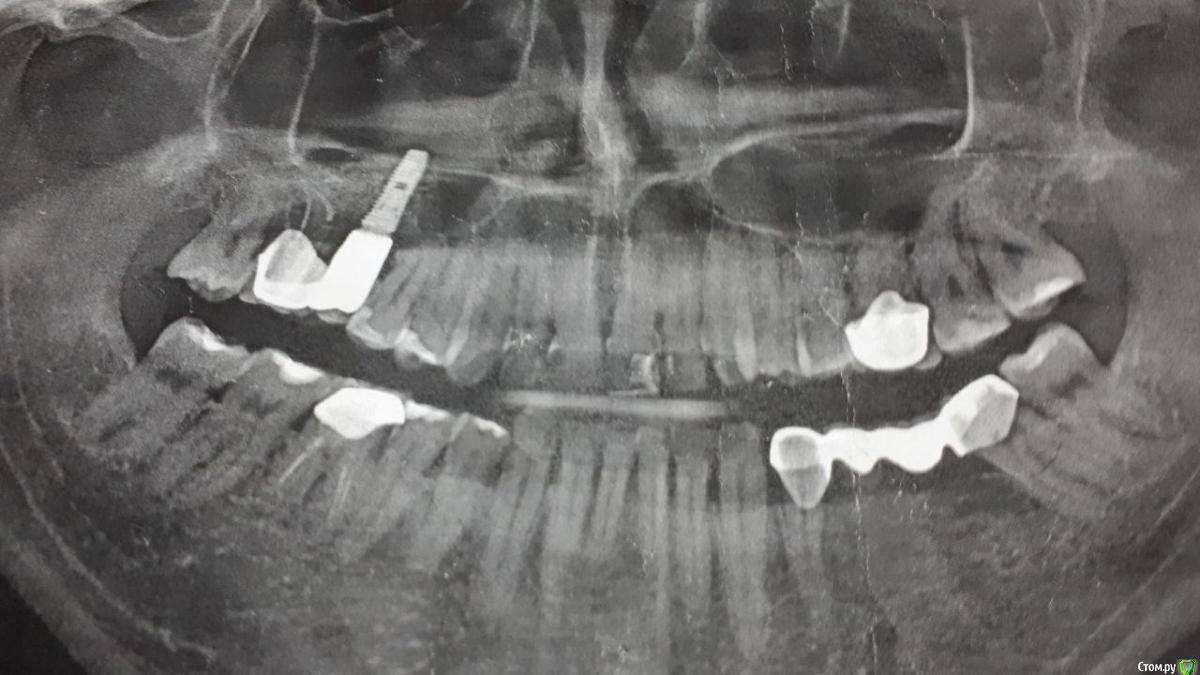

Доброго времени суток! Будьте добры, посоветуйте хорошего, опытного хирурга-пародонтолога, работающего поближе к Магнитогорску.- Челябинск, Екатеринбург, Уфа, Оренбург, Самара, который смог бы помочь мне с моей проблемой,а проблема заключается в генерализованной рецессии. Заранее Спасибо!